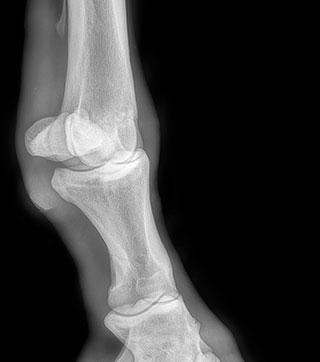

Radiología

Contamos con el equipo de radiología digital inalámbrico más avanzado del país, el cual permite obtener las mejores imágenes en el acto y compartirlas vía mail. Realiza radiografías de miembros, columna, cabeza, cuello y hombro.